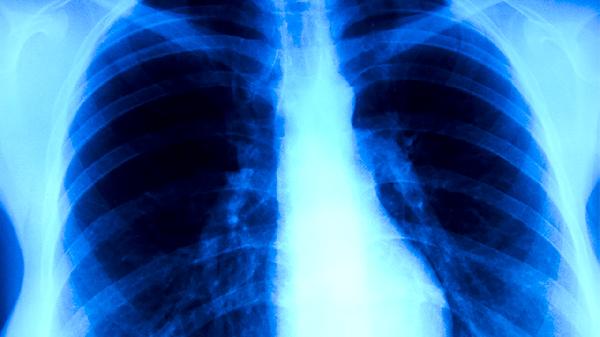

肺積水胸腔積液多數(shù)情況下無需手術(shù),可通過胸腔穿刺引流、藥物治療、病因治療等方式緩解。是否手術(shù)主要取決于積液量、病因及對保守治療的反應(yīng),常見影響因素有感染性積液、惡性腫瘤、心力衰竭、低蛋白血癥、結(jié)核性胸膜炎等。